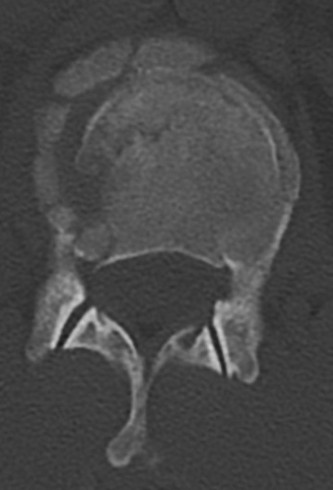

Initial trauma radiographs demonstrated a loss of anterior and middle column height at L1, with a focal kyphotic deformity. However, plain films are vastly insufficient for definitive surgical planning in thoracolumbar trauma. A high-resolution, fine-cut Computed Tomography (CT) scan of the entire spine was obtained. The CT images confirmed an L1 burst fracture with severe comminution of the vertebral body. Sagittal and axial reconstructions revealed 50% canal compromise secondary to a large retropulsed bone fragment originating from the posterosuperior aspect of the L1 vertebral body. Furthermore, the CT demonstrated 25 degrees of segmental kyphosis measured from the superior endplate of T12 to the inferior endplate of L1.

A critical finding on the axial CT slices was a vertical, split fracture propagating through the L1 lamina. This is a highly significant morphological feature. A lamina fracture in the setting of a burst fracture with retropulsion strongly correlates with a dural tear and potential entrapment of the cauda equina nerve roots. When the vertebral body bursts posteriorly, the pedicles are driven outward, and the lamina fractures as the spinal canal attempts to expand to accommodate the retropulsed bone. If the dura is lacerated, nerve roots can herniate through the dural defect and become incarcerated in the laminar fracture site.